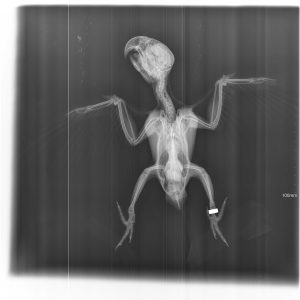

El diagnóstico por imagen es una herramienta fundamental en la medicina veterinaria moderna, ya que permite evaluar de forma precisa y no invasiva las estructuras internas del paciente. A través de técnicas avanzadas como la radiografía digital y la ecografía, es posible identificar alteraciones anatómicas y funcionales que facilitan un diagnóstico temprano y un manejo clínico más eficaz.

Nuestro servicio en Mastervet está orientado a ofrecer estudios de alta calidad, con equipos actualizados y protocolos adaptados a cada caso. Realizamos evaluaciones completas que incluyen la interpretación detallada de las imágenes y la emisión de informes clínicos claros, contribuyendo a la toma de decisiones terapéuticas.

Trabajamos en estrecha colaboración con veterinarios clínicos para asegurar una correcta correlación entre los hallazgos de imagen y la situación clínica del paciente, optimizando así el abordaje diagnóstico y el seguimiento evolutivo.